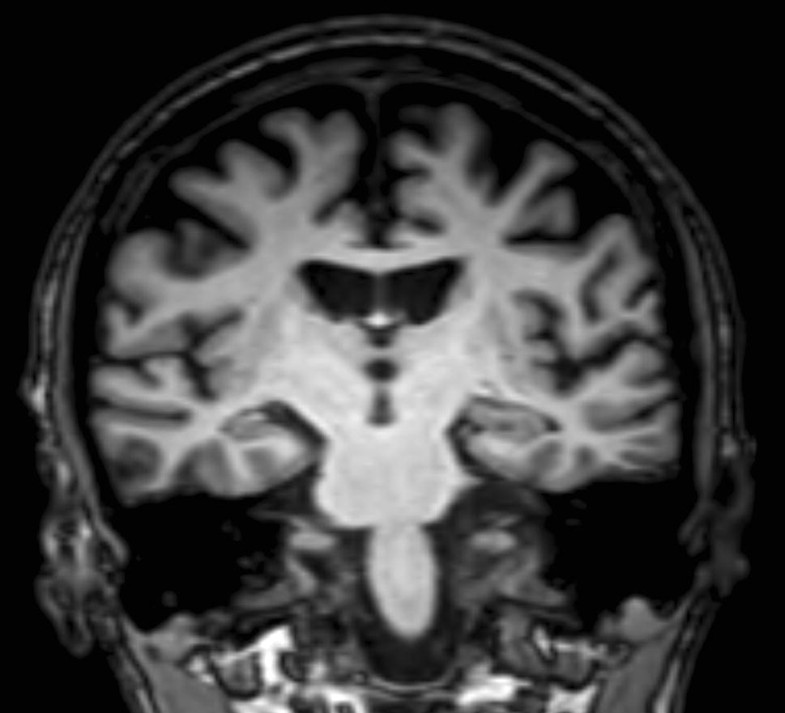

Image Niemann Pick Type C Mri Brain Diffuse moderate brain atrophy and mild periventricular and subcortical. Mri and ct scans are not very useful for diagnosis,. The manifestations in the perinatal. The diagnosis is often delayed because of non. In this study, we examined brain iron. Hearing tests (audiogram and/or brainstem evoked potentials) often show abnormalities. Sometimes it can affect the lungs. Niemann Pick Type C Mri Brain.